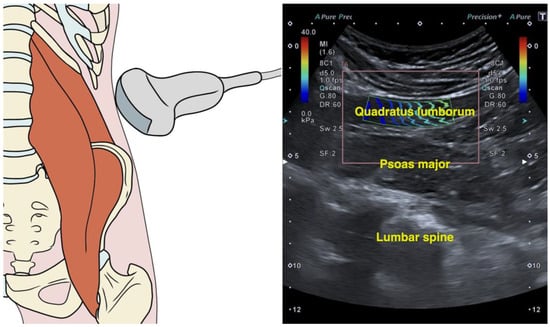

The transducer was initially positioned superior to the iliac crest along the mid-axillary line. Then, its cranial aspect was pivoted posteriorly by approximately 20° to achieve visualization of the L4 vertebra at the center of the imaging field (Figure 1). In this location, the quadratus lumborum was identified as the relatively hypoechoic muscle overlaying the psoas major muscle (visualized as the muscle overlying the vertebral bodies). Lastly, the region of interest was established on the center of the muscle, covering at least 50% of the muscle and excluding the fasciae, using a freely drawn quantification box (Figure 1). The side examined in patients reporting unilateral pain was the symptomatic one. In patients reporting bilateral pain, the mean average of both sides was calculated. The rationale behind this decision was that duplicating patients (by treating the left and right sides as separate measures) in the correlation analysis would introduce several methodological challenges and biases. First, it would violate the assumption of independence required for correlation analyses, as the left and right sides of the same patient are inherently related due to shared physiological, biomechanical, or pathological factors. This lack of independence could distort the results and artificially inflate the strength of observed correlations. Additionally, this approach would lead to an overrepresentation of individual data, as each patient would effectively contribute more than one data point to the analysis. This would create an imbalance, giving undue weight to patients with bilateral data compared to those with unilateral data, which would reduce the generalizability of the findings.

Figure 1. Illustration indicating the transducer placement, the corresponding shear wave elastography image, and the region of interest for measuring quadratus lumborum stiffness.